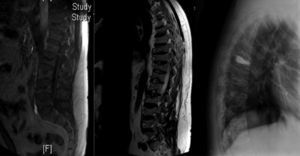

Observación clínicaVarón de 40 años, sin antecedentes de interés, que ingresó en julio de 2013 por dorsalgia intensa de una semana de evolución. El estudio radiológico reveló la presencia de aplastamientos vertebrales múltiples (fig. 1). La densitometría ósea mediante absorciometría radiográfica de doble energía confirmó la presencia de OP lumbar (T score de −3,37). Se descartaron causas secundarias de OP del varón (infección por VHC, hipogonadismo, hiperparatiroidismo...) así como procesos linfoproliferativos y otras causas tumorales. El paciente precisó vertebroplastia de D7 por dorsalgia refractaria a mórficos (fig. 1); en este momento se decidió iniciar tratamiento con teriparatida subcutánea. Dada la negatividad del extenso estudio realizado, se determinaron niveles de triptasa sérica, que resultaron persistentemente elevados (cifras en torno a 53,9 mcg/l [5,5-13,5]). En consecuencia, se realizó aspirado y biopsia de médula ósea que resultaron compatibles con mastocitosis. Por citometría se detectó un 0,13% de mastocitos, de los cuales el 99,5% tenían un fenotipo activado y el 0,5%, CD25. Se detectó la mutación D816V (A7176T) de c-KIT en la médula ósea total, restringida al mastocito (TaqMan).

RNM de la columna dorso-lumbar: se aprecia disminución de altura de cuerpos vertebrales dorsales y lumbares. El cuerpo vertebral D7 está notablemente disminuido de altura y presenta alteración en la intensidad de la señal. Hay cambios similares pero menos notorios en el borde superior de D11 y L2.

Rx lateral de la columna dorsal: vertebroplastia a nivel de D7.